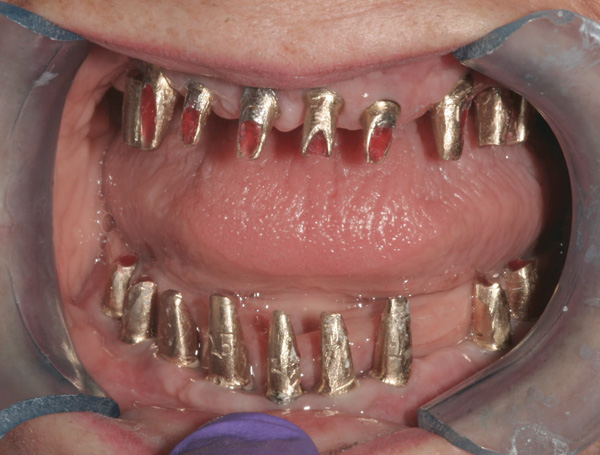

Background: In this case, the patient had a failing mandibular and maxillary dentition due to caries secondary to radiation-induced xerostomia. The patient had had a radical neck dissection to remove a squamous cell carcinoma of the throat 9 years prior to his prosthodontic consultation with the authors. The patient reported a history of radiation therapy following surgery, but did not have a shielding stent. A staged approach was used so as to avoid removable prosthetics on his severely dry soft tissues. He chose to treat his mandibular issues first. Figure 9 shows healing abutments next to the temporarily retained natural teeth, and Figure 10 shows the first-stage custom abutments inserted with relatively good gingival contour and no recession. Recession was clearly seen around all first-stage abutments following adjacent extractions and second-stage implant placement (Figure 11).

Figure 9 Healing abutments.

Figure 9

Figure 10  First-stage custom abutments.

Figure 10

Figure 11 Recession evident around first-stage abutments following adjacent extractions and second-stage implant placement.

Figure 11